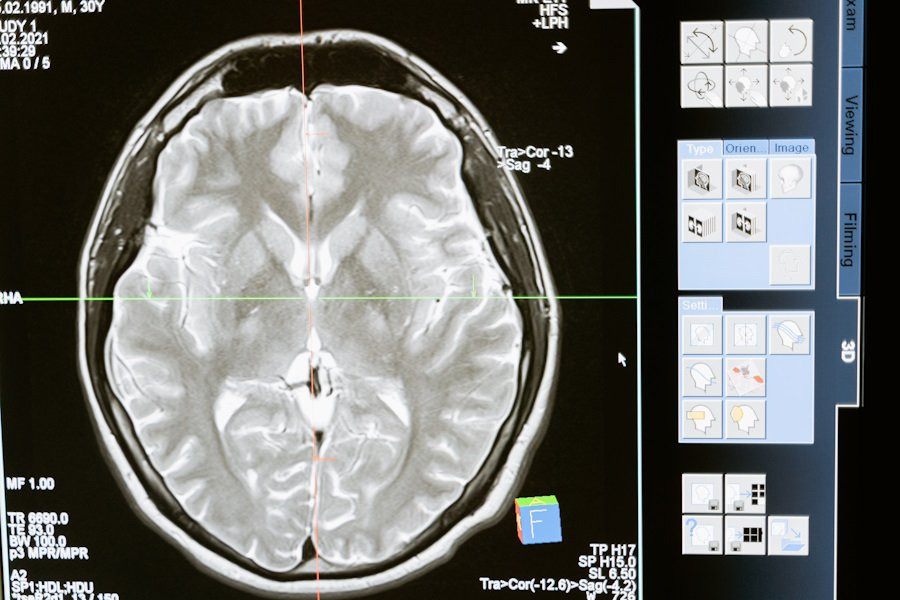

Фото из открытых источников

Российские ученые разработали уникальную платформу для борьбы с одной из самых опасных опухолей мозга — глиомой. Этот проект, направленный на улучшение диагностики и лечения, разрабатывается под руководством профессора Галины Павловой в НМИЦ нейрохирургии имени академика Н.Н. Бурденко Минздрава РФ.